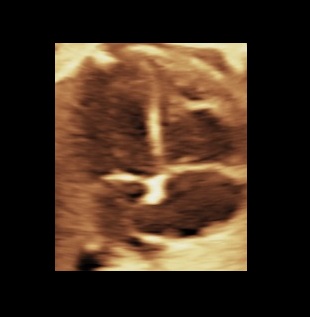

4. Four anatomically distinct chambers present

Two atria (approx. equal in size) and two ventricles (approx. equal in size). The anatomic left atrium has a hook shaped appendage, while the anatomic right atrium has a broad pyramidal shaped appendage. Also, the left atrium receives the four pulmonary veins, two of them – the inferior ones – can be identified in the four chamber view. The anatomic left ventricle forms the cardiac apex, while the anatomic right ventricle contains the moderator band.

5. Normal cardiac crux

In normal cases the septum primum can be identified near the crux. The tricuspid valve leaflet inserts on ventricular septum closer to cardiac apex than does mitral valve (differential offsetting of the AV-valves). Both valves open and move freely. Also the ventricular wall has to be in contact with the crux.

6. Foramen ovale leaflet in left atrium

Flow from right to left on color mode.

7. Ventricular septum intact

From apex to crux. Note that the four chamber view can detect only inlet-type and some of the muscular-type septal defects.

8. Cardiac wall

No hypertrophy of the ventricular wall, no pericardial effusion.

MB: moderator band, RV: right ventricle, TV: tricuspid valve, RA: right atrium, Fo: foramen ovale, SP: septum primum, PV: inferior pulmonary veins, Ao: aorta, LA: left atrium, MV: mitral valve, LV: left ventricle, VS: ventricular septum.